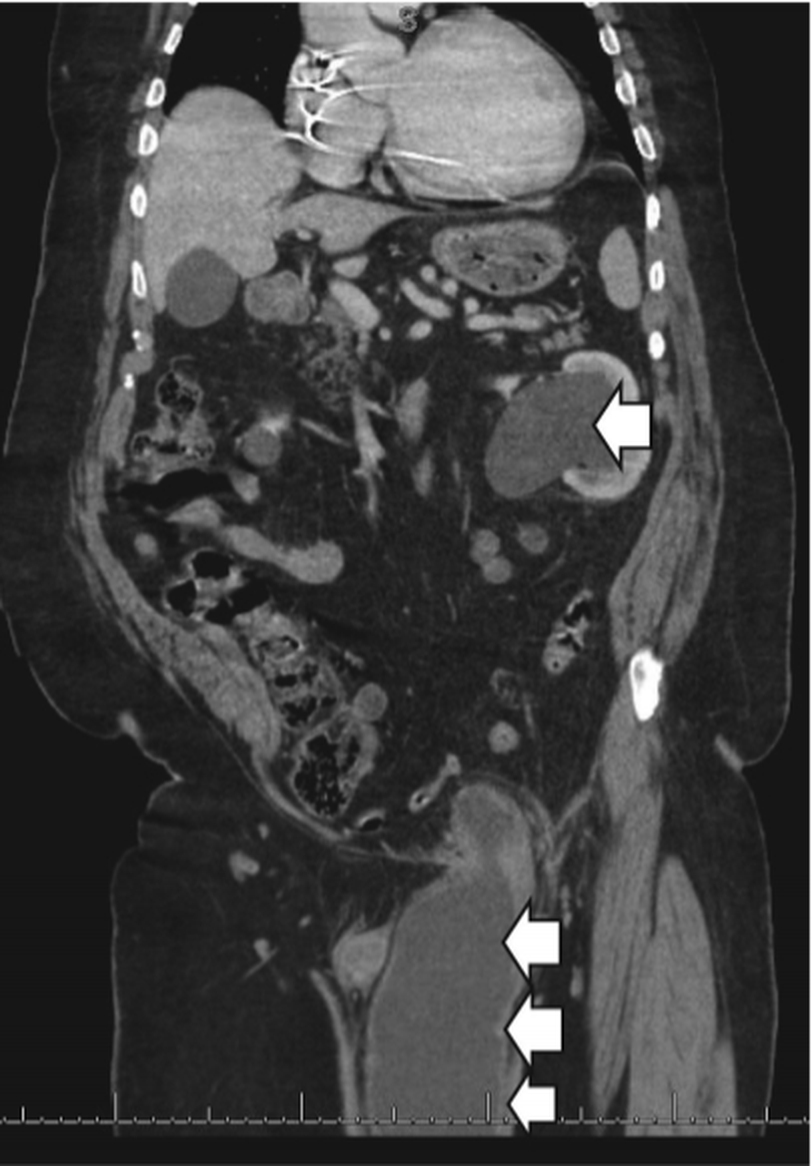

Herniation of urinary bladder into inguinal canal is a rare occurrence, however, when it occurs, it presents with signs and symptoms of urinary obstruction along with swelling in scrotal region. An article reported a rare case of complete bladder herniation in presence of prior neurologic deficit secondary to stroke as well as previous history of surgical repair of hernia. A 74 years old, unidentified male, suffered from acute urinary retention while he was straining in order to defecate. The scrotal swelling developed suddenly along with urinary obstruction. Attempts for catheterization were unsuccessful. Investigative imaging revealed complete herniation of bladder into left inguinal region with severe obstructive uropathy with bilateral hydronephrosis secondary to obstructed ureters. Specialists from general surgery and urology were consulted. Open repair of incarcerated inguinal hernia along with cystorrhaphy was performed. Patient recovered without developing further complications with no voiding problems. Source Massive bladder inguinal hernia leading to acute urinary retention https://www.sciencedirect.com/science/article/abs/pii/S0735675720305416 Image via https://www.sciencedirect.com/science/article/abs/pii/S0735675720305416